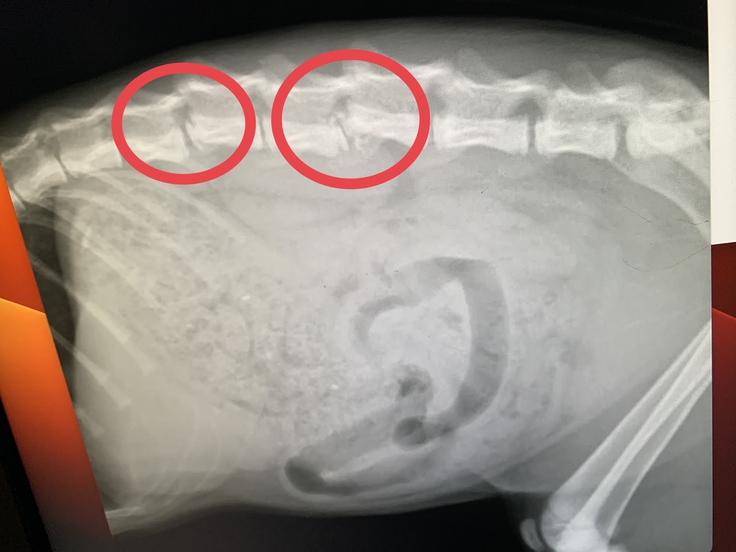

診断内容は背骨2本の骨折及び脱臼、内臓損傷や外傷は無し。

下半身が麻痺しており痛覚も無い様子でした。

治療には全身麻酔での手術(金属のボルトを使用し背骨を矯正)が必要とのことで、治療を施さない限り下半身が動く見込みは無いとのこと。

レントゲン画像や診断内容は前日診ていただいた病院から伝わっていた様で、下半身の回復を望むのであればやはり手術が必要であることを伝えられました。

さといもの成長への影響を考慮し、ボルトではなくワイヤーでの固定へ切り替えられたそうです。

残念ながら現段階では未だ下半身は動かすことが出来ていません。

術後1ヶ月以内に動くことが無ければ、恐らく今後動く見込みは無いとのことでした。